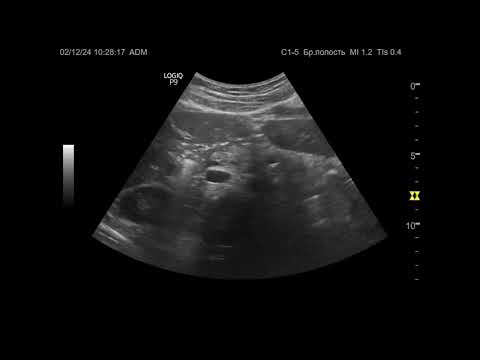

Ультразвуковая диагностика. Доктор Иогансен. Видеопримеры. Выпуск 113. Аутоиммунный тиреоидит (4).

Представлены новые видеопримеры аутоиммунного тиреоидита, выявленного при УЗИ. Ссылка на Дзен: Ссылка на RuTube: Ссылка на ВК видео: Ссылка на YouTube: / @dr.johansen